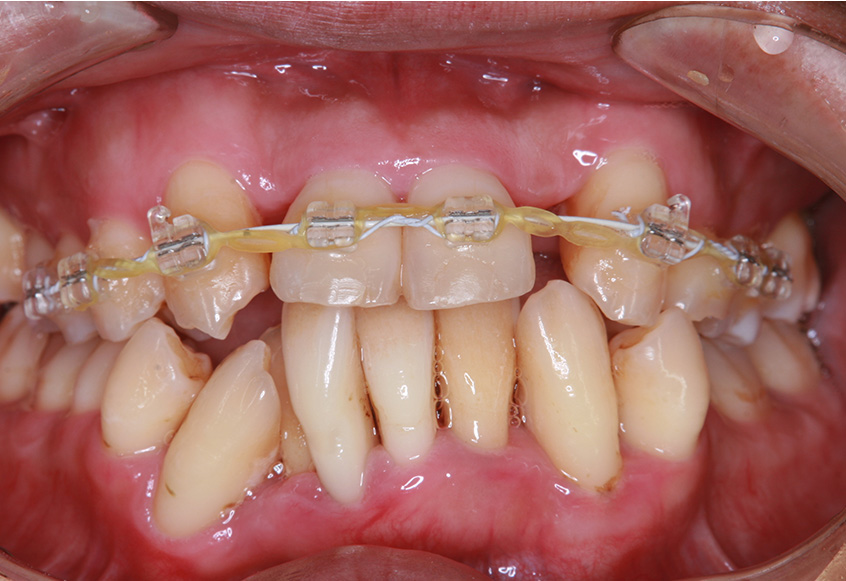

親知らずの痛みがなくなった患者さんは、昔から歯並びが気になっていることを打ち明けてくれました。特に上の歯が少し前に出ていたり、隙間があったりしている点を治したいそうです。そこで、まず上の歯並びの矯正治療を開始しました。

最初のお口の中 ワイヤー装着して治療を開始